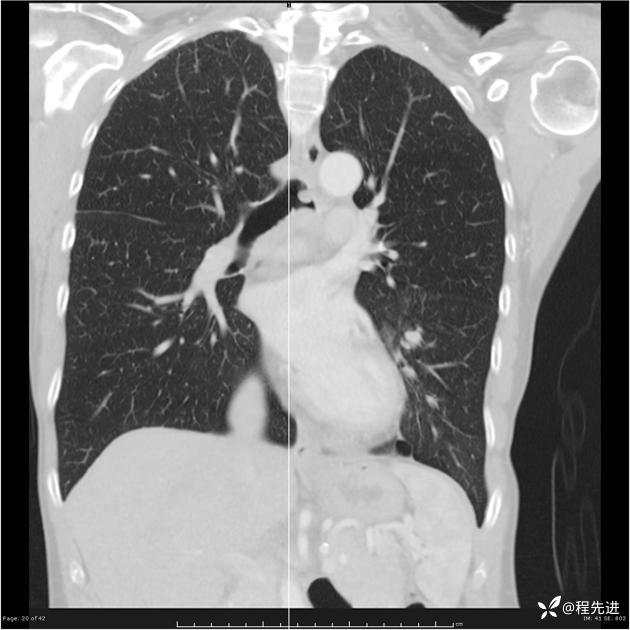

病例女,53岁,气管、左主支气管、下叶支气管内结节,乳头状瘤?期待你的精彩解读

女,53岁

乳头状瘤?